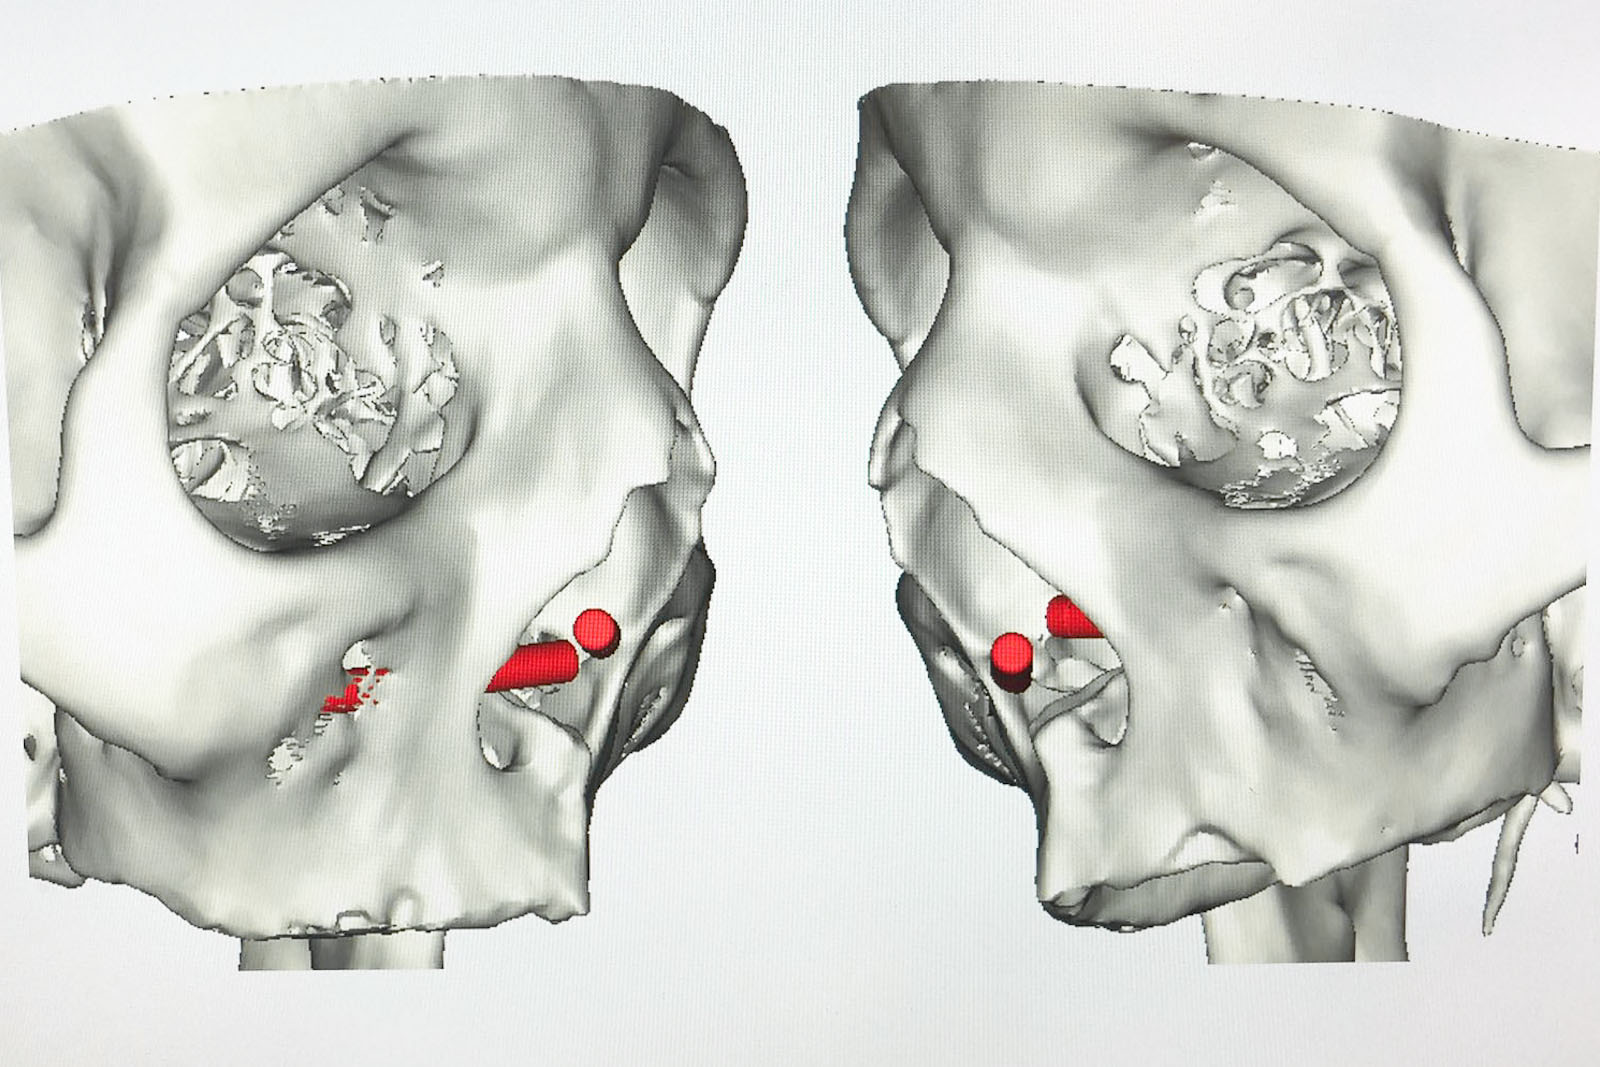

Chory po resekcji tkanek/narządów twarzoczaszki wymaga wnikliwej diagnostyki obrazującej zakres ubytku oraz stan podłoża kostnego. Wykonuje się zdjęcia radiologiczne RTG pantomograficzne szczęk OPG, konwencjonalną tomografię komputerową CT, stożkową tomografię komputerową CBCT, ukazującą trójwymiarowy obraz twarzoczaszki, oraz w razie potrzeby rezonans magnetyczny NMR. Możliwy jest również druk modeli 3D w skali 1:1 dowolnej części twarzoczaszki.

Diagnostyka ma za zadanie wykluczenie wznowy wyciętego nowotworu oraz pomoc w ocenie tkanki kostnej w okolicy ubytku. Ocena kości pozwala na zaplanowanie zabiegu wszczepienia implantów jako przyszłego fundamentu niezbędnego dla mocowania protez poresekcyjnych lub epitez twarzy.

Należy dokonać doboru odpowiedniego systemu i rodzaju implantów przydatnych do przyszłego umocowania protez poresekcyjnych. Systemy implantologiczne używane dla tych celów to:

- implanty czaszkowe – krótkie, zwykle o długości 3 mm i 4 mm, w formie śrub, które wszczepia się w kości pokrywy czaszki oraz twarzoczaszki w zależności od potrzeby oraz rodzaju braku tkankowego; system implantów czaszkowych oferuje komplementarne rozwiązania protetyczne typu belki Doldera, zaczepy i magnesy, które umożliwiają stabilne umocowanie protez zewnętrznych, np. ucha czy nosa

- implanty Zygoma – długie, 30–52,5 mm, przeznaczone do mocowania w strukturze kości jarzmowej; w przypadku istnienia ubytku poresekcyjnego szczęki mocuje się je w kikucie kości jarzmowej, która pozostaje po resekcji; implanty Zygoma umożliwiają stabilne umocowanie protez poresekcyjnych po wycięciu częściowym lub nawet całkowitym szczęk ze względu na swoją konstrukcję i wymiar. Pomocne bywają również przy mocowaniu epitez np. nosa (czytaj dalej...)

Zastosowanie współczesnych technik obrazowania trójwymiarowego umożliwia precyzyjne zaplanowanie pozycji implantów czaszkowych, tak by ektoprotezę stabilnie osadzić na podłożu.